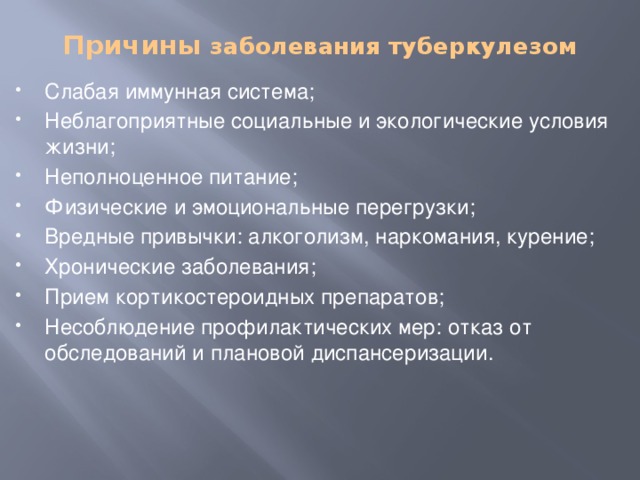

Симптомы туберкулеза: Как распознать и что делать

Раздел: Визуальные уроки